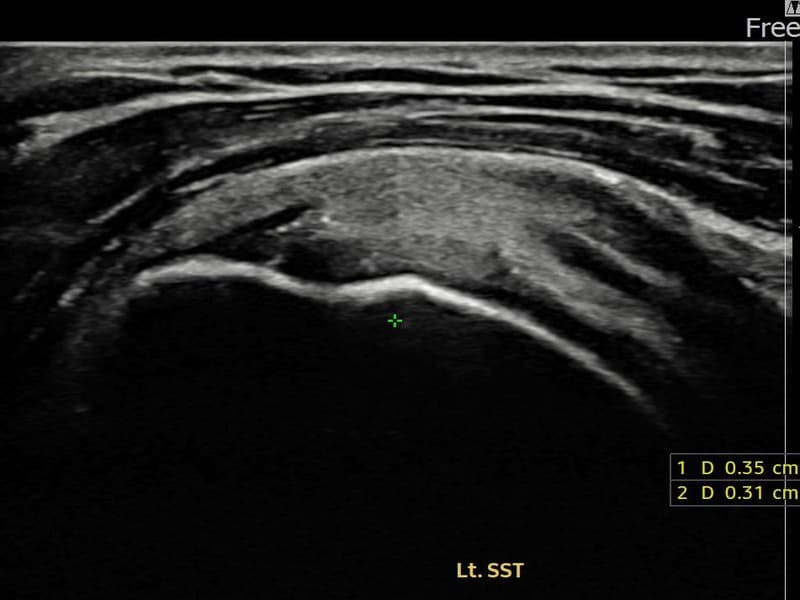

超声确认左侧 冈上肌腱 附着部部分撕裂(5mm × 3mm (肌腱厚度约25%缺损))。缩小缝合术后肌腱连续性恢复,患者回归正常生活。

术前

术前超声确认左侧 冈上肌腱 附着部部分撕裂,左侧冈上肌腱回声不连续伴肌腱缺损(5mm × 3mm (肌腱厚度约25%缺损))。术后超声显示撕裂部位充满再生组织,肌腱连续性恢复,回声模式正常化。